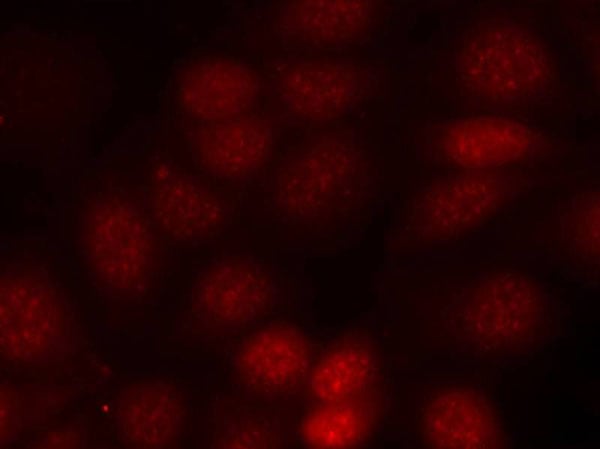

IHC (Immunohistochemistry)

(Immunohistochemical analysis of paraffin-embedded Human Lung Carcinoma Tissue using P70 S6 Kinase Mouse mAb diluted at 1:200.)